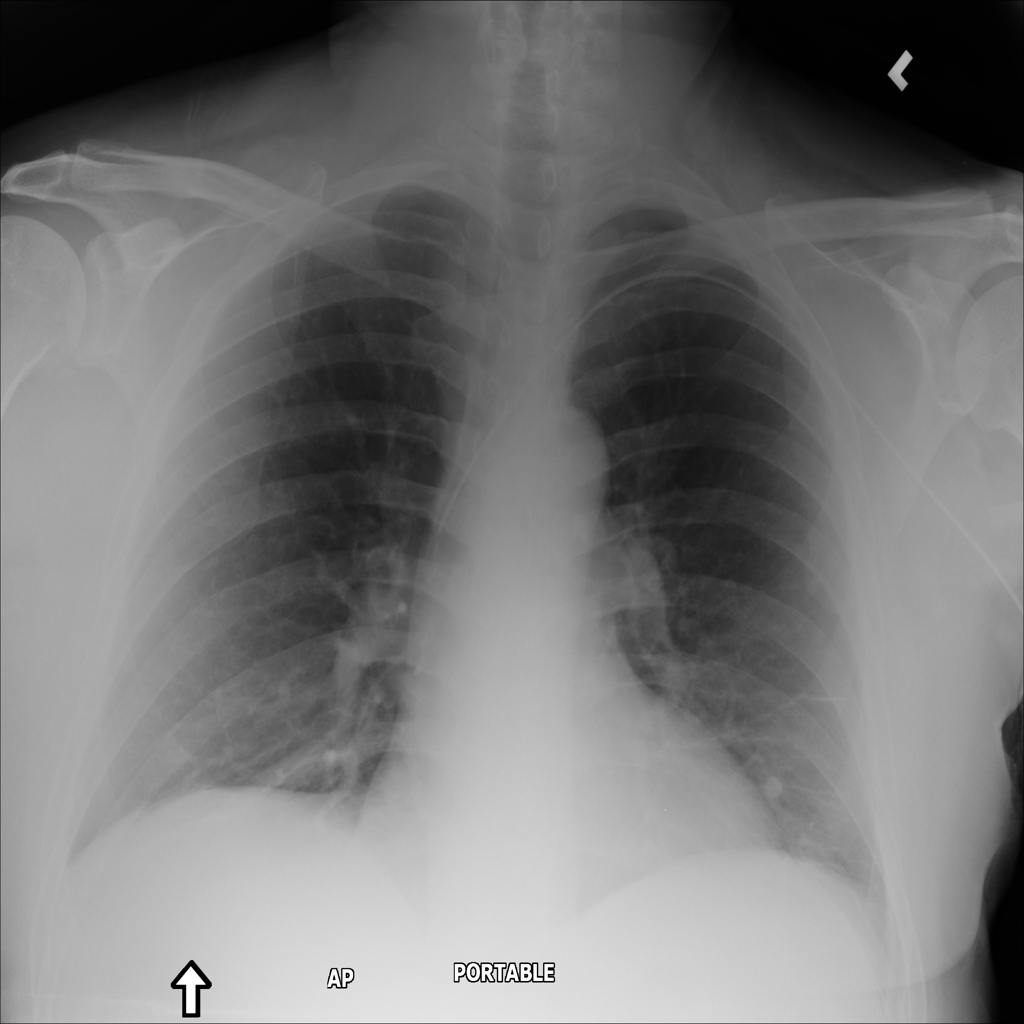

PAT-3384 · IMG-054Atelectasis

PAT-3384 · IMG-054

AP